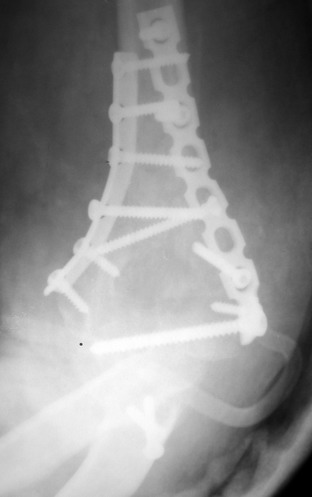

Остеосинтез закрытый (если так можно выразиться), т.е. без

разрезов. Длительность операции - около 1,5 часа со студентом.

6 щелчков ЭОПом.